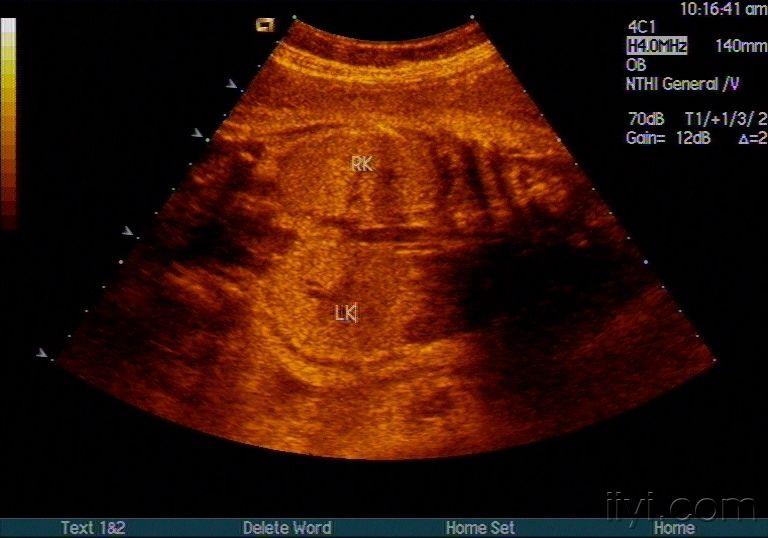

胎儿多囊肾

图片尺寸720x576